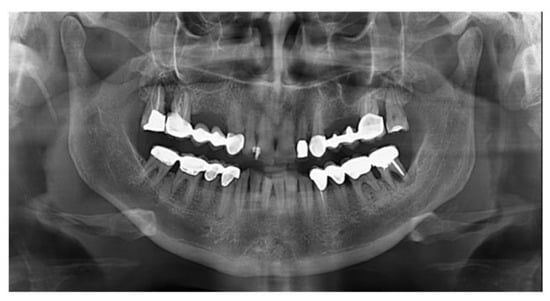

Long-Term Outcomes of Implants Placed in Maxillary Sinus Floor Augmentation with Porous Fluorohydroxyapatite (Algipore® FRIOS®) in Comparison with Anorganic Bovine Bone (Bio-Oss®) and Platelet Rich Plasma (PRP): A Retrospective Study

2. Materials and Methods

3. Results